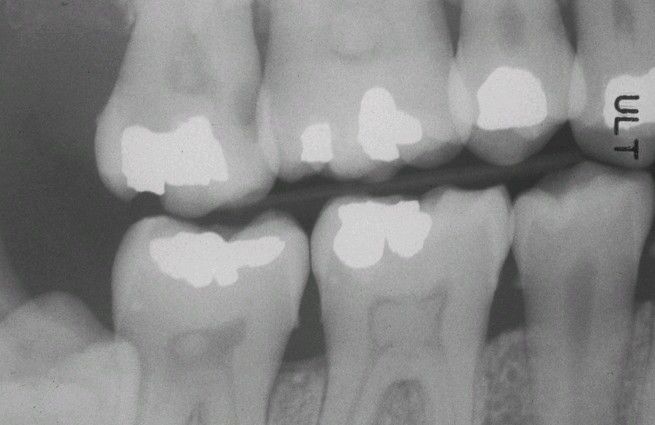

Pulp Stones

. Multiple teeth demonstrating radiographically obvious calcifications within the pulp chambers.